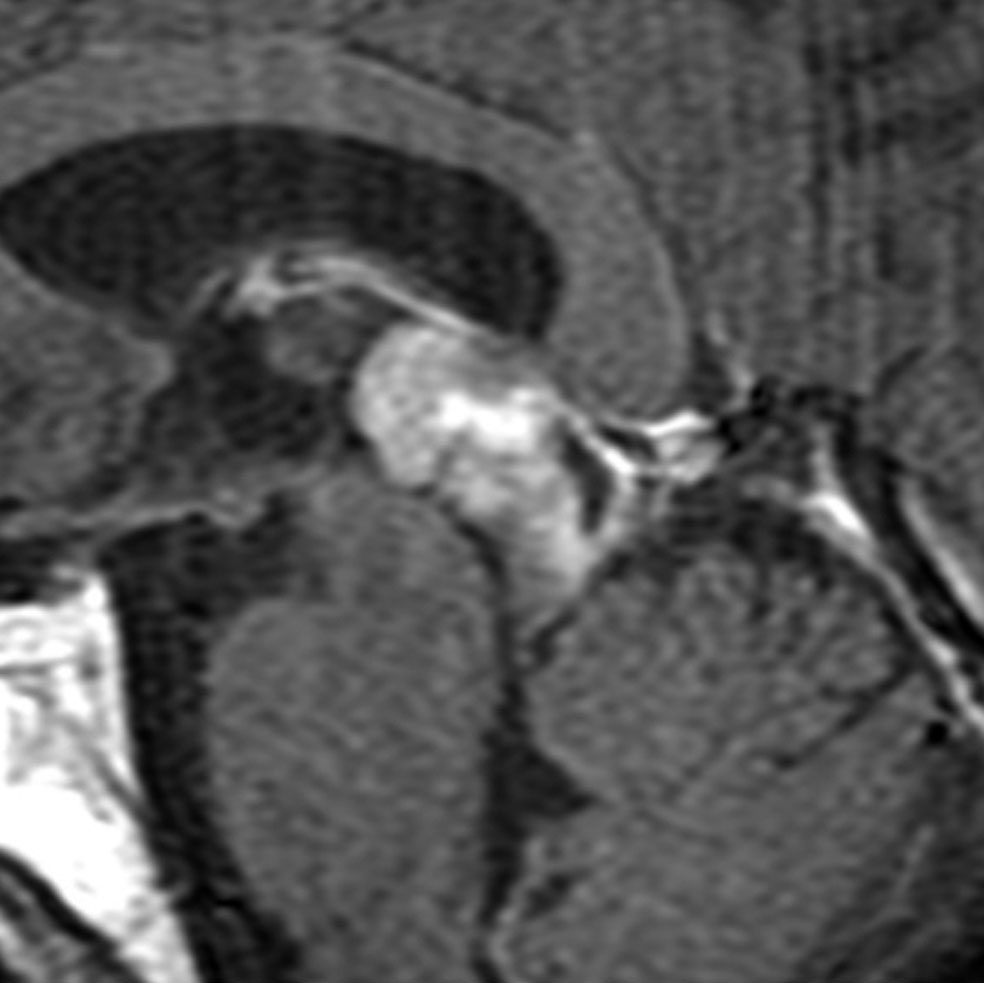

tectal gliomaに間違えそうなPPTID 松果体実質腫瘍

上段のガドリニウム増強MRIでは松果体腫瘍に見えやや境界が不明瞭なので,年齢からはPPTIDが疑われます。しかし,CISSの画像で,中脳上丘との境界がなく中脳腫大があるようにみえ,テクタールグリオーマを疑って経過観察しました。腫瘍がゆっくり増大したので摘出したところPPTIDという診断がつきました。